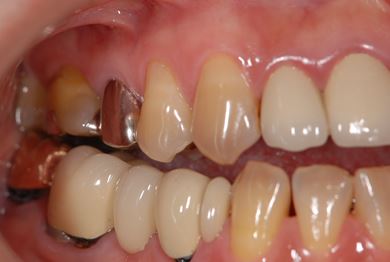

性別/年齢 女性 / 42歳

主訴 右下の奥歯をセラミックで治療したい。

治療内容 メタルボンドセラミック(クラウン1本、ブリッジ3本、メタルボンドセラミック土台1本)+ハイブリッドセラミックインレー1本

総治療費 478,905円

治療期間 6ヶ月